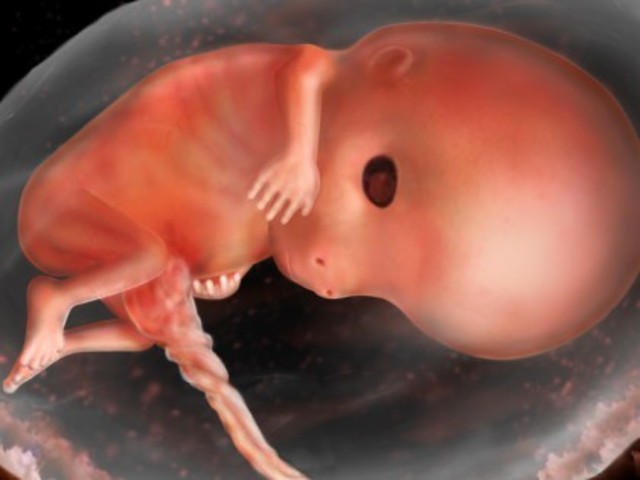

Month One

Size is about 1/4 of an inch long. Fetus is made up of three layers- ectoderm, mesdoderm, and endoderm that will eventually form different body systems. The ectoderm develops into the epidermis, nervous tissue, and sensory organs. The mesoderm develops into connective tissue, muscle, bone, and the urogenital and circulatory system. The endoderm develops into the gastrointestinal tract, the lungs, and associated structures.

The neural tube will eventually form the spinal cord. At this point basic facial features are also beginning to develop. The digestive tract has also begun development, as well as the spine.